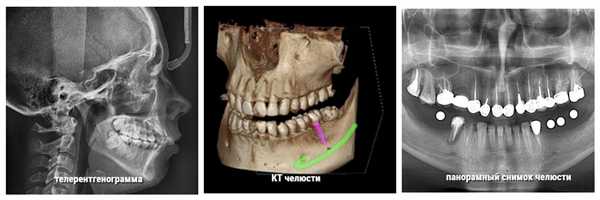

Диагностикой и коррекцией неправильного прикуса занимается ортодонтия. На первом этапе происходит подготовка к ортодонтическому лечению, которая включает в себя комплекс диагностических мероприятий, по результатам которых и определяется степень сложности терапии. Для этого делают ортопантомограмму (панорамный снимок), радиовизиографию или же используют данные компьютерной томографии. Снимки позволяют увидеть и оценить степень изменений в зубочелюстной системе.

КТ черепа. Прогнатический прикус, зубы верхней челюсти (красная стрелка) выстоят кпереди (этот же пациент).

С целью проведения подробных расчетов и составления грамотного плана лечения проводится панорамный снимок (ортопантомограмма), рентгенография черепа в боковой проекции (телерентгенограмма), фотографирование лица в фас и профиль. На основании снятого альгинатного слепка изготавливается диагностическая гипсовая модель зубных рядов. Для получения дополнительных данных о неправильном прикусе у детей может потребоваться компьютерная томография, миография. После сбора всех необходимых данных производится компьютерное моделирование результатов лечения.

Неправильный прикус у взрослого и ребенка диагностируется с помощью следующих методов исследования:

- панорамный снимок челюсти;

- КТ челюсти;

- телерентгенограмма (ТРГ-снимок).

Перечисленные материалы дают опытному врачу достаточно информации, чтобы определить проблемы с прикусом и составить актуальный план лечения.

Разные виды исследований прикуса